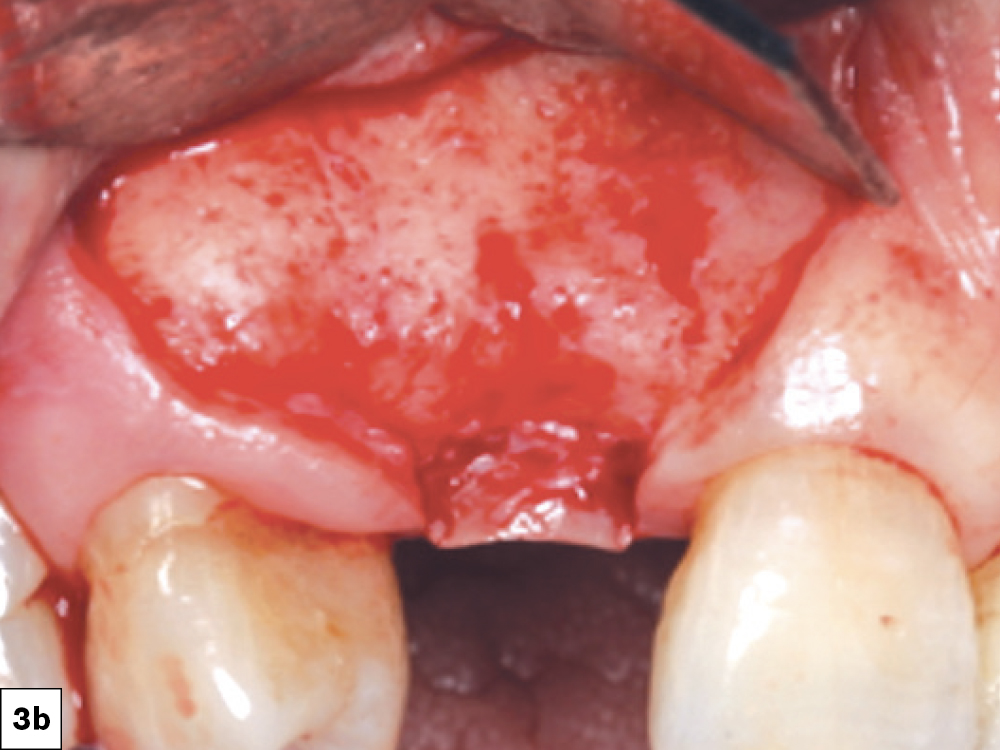

2. Broad-Based Flap Design

A broad-based incision consists of a flap design which has a base that is larger than the apex (ridge). This incision design allows for better preservation of blood supply to the surgical site, which is crucial in preventing ischemic necrosis and decreasing the likelihood of ILO (Figs. 3a, 3b).

Incision design in keratinized tissue and broad-based flap design.

Figures 3a, 3b: Incision design in keratinized tissue and broad-based flap design.